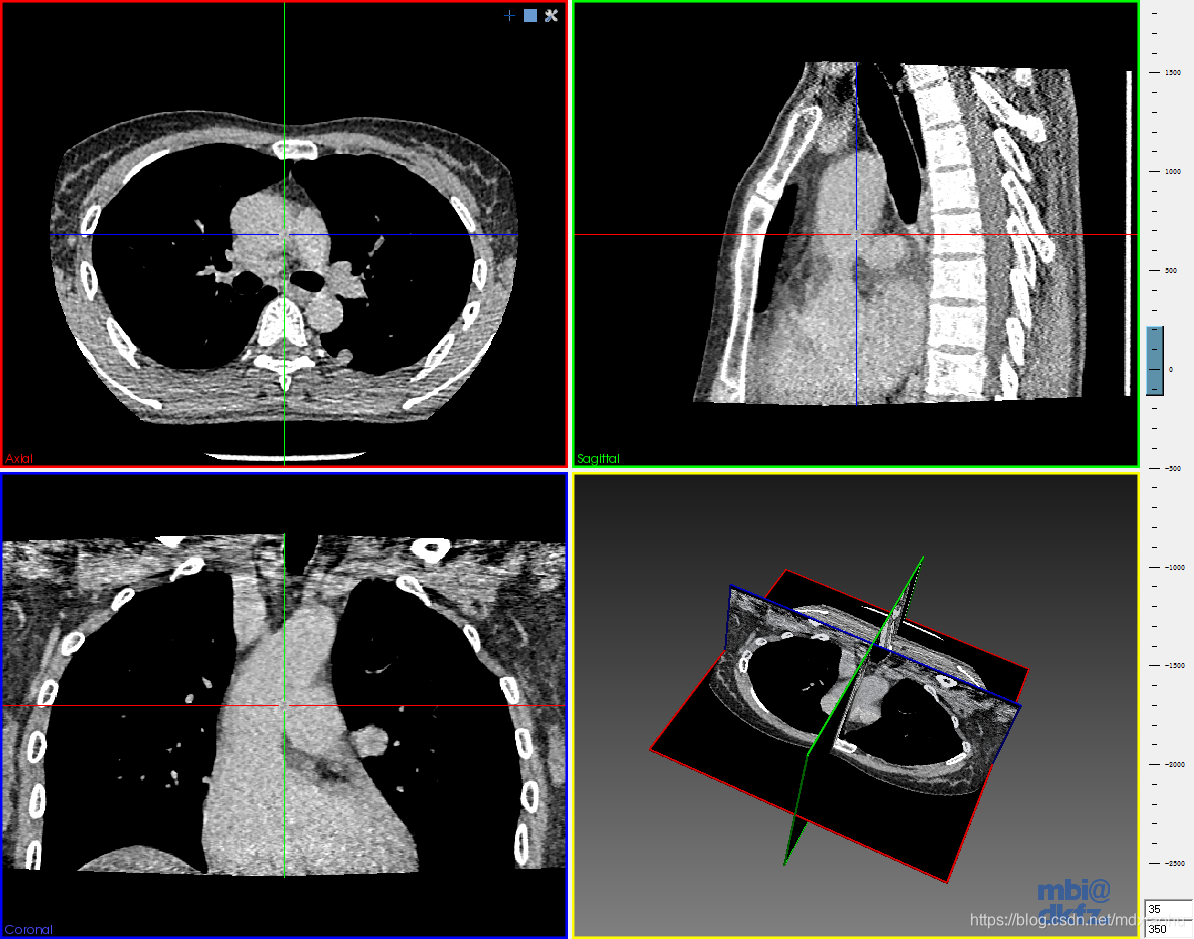

肺部CT序列图:

都是没有经过分割的。

本文分享了一系列医学影像处理的学习资源,包括未经分割的肺部CT序列图、已分割及未分割的肝脏CT序列图和颅脑mhd图像等。所有资源均可通过提供的百度网盘链接下载。